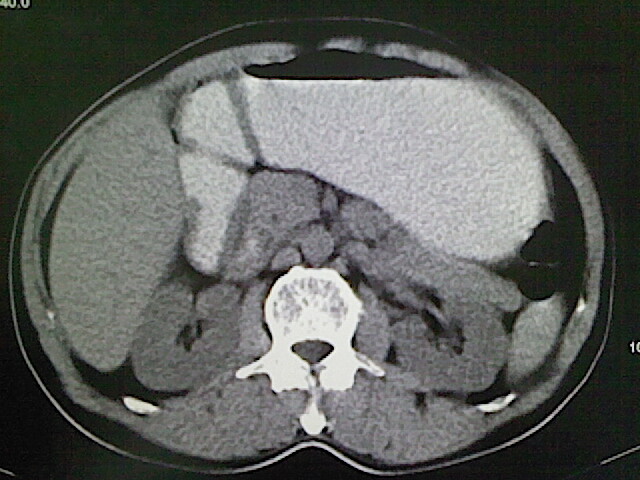

标题: CT18630:男,54岁,乙肝,大家看怎么样? [打印本页]

男,54岁,乙肝,大家看怎么样?

肝脏的要有增强敢说话

未见明确异常;建议必要时行ct增强扫描检查。